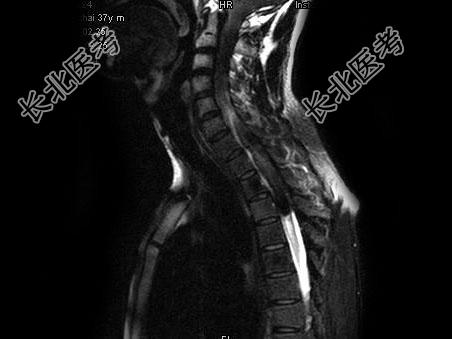

单项选择题男,37岁, 肢体活动不利、酸胀1年余,MRI扫描见椎管内长条形T1和T2高信号, 脂肪抑制序列呈低信号,应考虑为 ( )